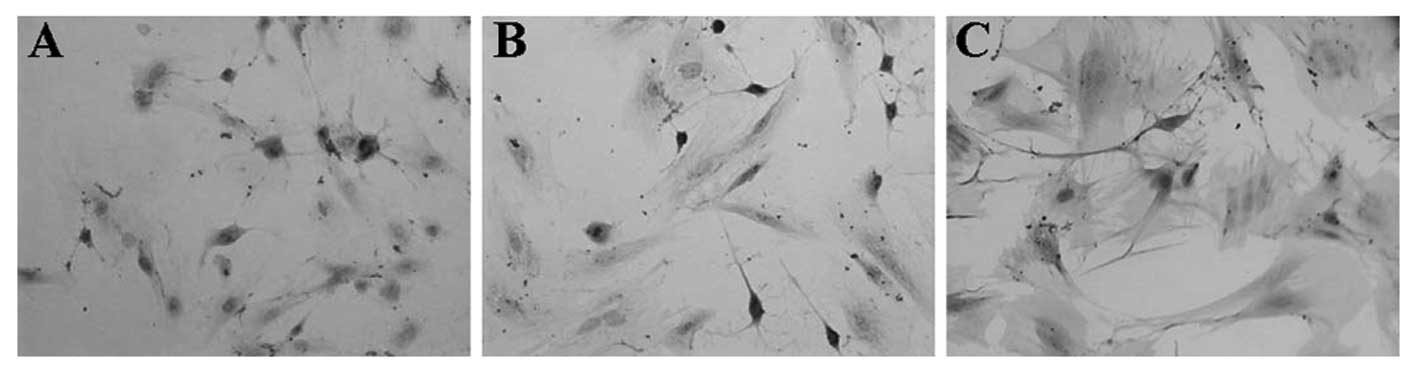

Reverse transcription‑quantitative polymerase chain reaction (RT‑qPCR) is a technique widely used for the quantification of mRNA transcription, It is well recognized that the reference genes used in RT‑qPCR require appropriate validation to ensure that gene expression is unaffected by experimental conditions. The differentiation of bone mesenchymal stem cells (BMSCs) into neurons is important in the treatment of nerve injury. In gene expression analysis of the differentiation of BMSCs into neuronal cells by, the commonly used reference genes for RNA analysis are often selected without any preliminary evaluation of their suitability. The present study aimed to evaluate the mRNA expression levels of 11 putative reference genes, including ACTB, ARBP, B2M, CYCA, GAPDH, GUSB, HPRT, PPIA, RPL13A, TBP and PGK1, in order to select the most suitable reference genes for RT‑qPCR of the differentiation of neuronal cells by BMSCs. The mRNA expression levels of the 11 putative reference genes were examined using RT‑qPCR in rat BMSCs differentiated into neuronal cells. Normal BMSCs and three types of rat BMSCs, which were chemically induced to differentiate into neurons using neurotrophic cytokines and co‑culture with retinal cells. The geNorm, NormFinder and BestKeeper software programs were used to select the most suitable reference genes. The results of the analyses using the three software programs demonstrated that RPL13A was the most stable among all the groups, while ACTB was the least stable. The combination of CYCA and PPIA reference genes contributed the most to increasing stability. The suitability of selected reference genes requires previous pre‑selection in every investigation. Based on the three software programs, RPL13A, and the combination of CYCA and PPIA were identified as the most suitable reference genes for RT‑qPCR in neuronal cells differentiated from BMSCs.